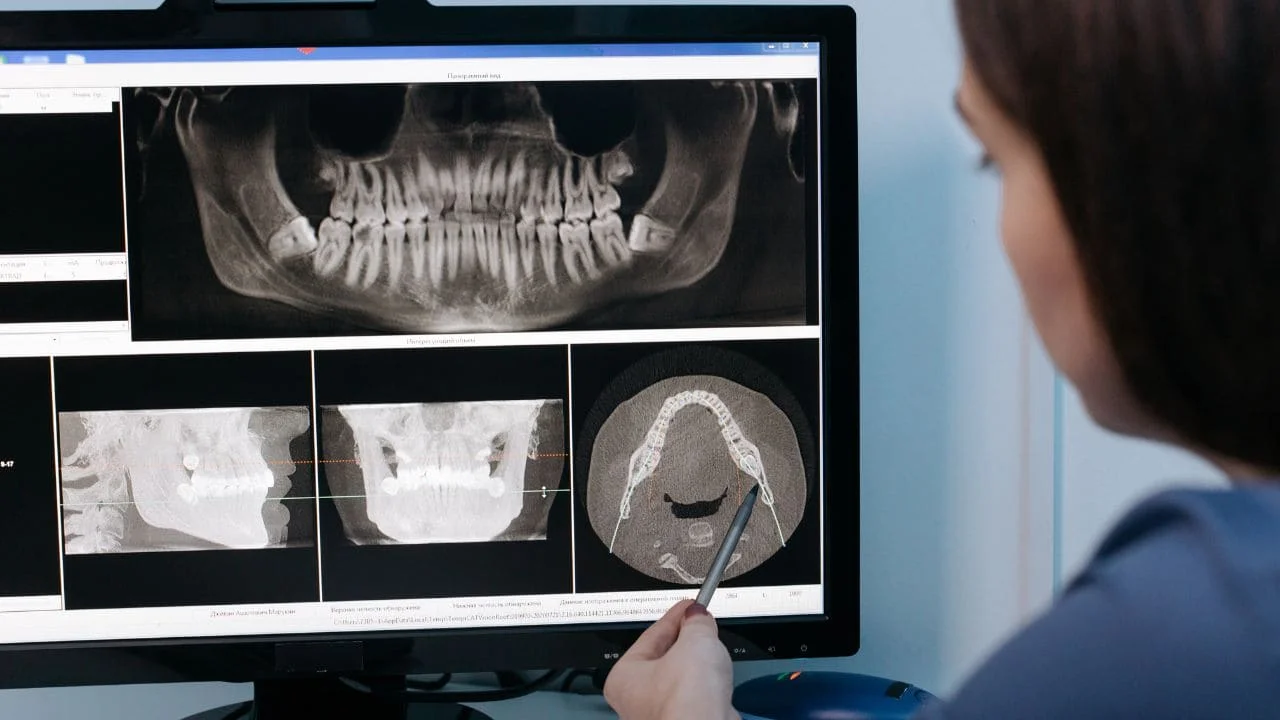

c. Examen radiographique :

- Complément indispensable à l’examen clinique, il donne de plus amples renseignements sur:

- Le stade de développement radiculaire.

- La présence ou non de fractures radiculaires.

- L’atteinte des structures parodontales.

- Volume de la chambre pulpaire

- La recherche des corps étrangers.

- Un film occlusal met en évidence le décalage existant entre la dent et l’alvéole et permet ainsi d’évaluer les luxations latérales, les fractures radiculaires et les fractures alvéolaires. Le rayon est dirigé sur la base du nez.

- Le maxillaire défilé (technique extra-orale):

-Connaître et évaluer un déplacement (la position de l’apex radiculaire par rapport au germe successionnel).

-La présence, ou non, de fracture de la lame osseuse vestibulaire.

- Radiographie panoramique, dans le cas d’une suspicion de fracture osseuse des bases maxillaires ou condyliennes.